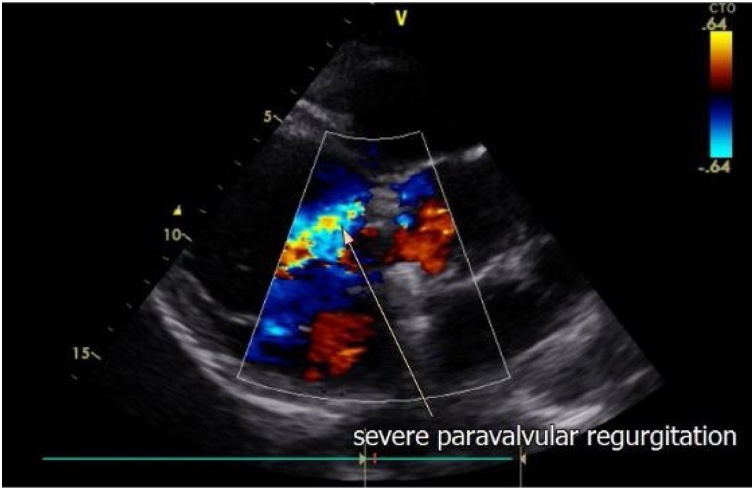

Fig. 2.

Severe paravalvular regurgitation.

We report a case of young man diagnosed with brucella prosthetic aortic valve endocarditis. A 37-year-old patient admitted initially in another medical center for history of fever of 3 months’ duration with night sweats and generalized fatigue. Patient reported raw milk intake. A diagnosis of brucellosis was made based on serology and he was started on doxycycline with rifampin. But no major improvement was noted after 2 weeks of treatment. The family transferred the patient to our hospital for continuity of care. Patient had persistent fever, and shortness of breath even at rest. He was found to be tachypneic, saturating 88 % on room air, tachycardic, and hypotensive. There was no urinary output. His past surgical history included an aortic valve replacement with mechanical valve implantation 20 years ago. An urgent transthoracic echo showed a total mechanical aortic prosthesis dehiscence with 4/4 para-valvular regurgitation, abscess in the aortic valve, with low ejection fraction (34 %) and moderate to severe pulmonary hypertension (Fig. 1, Fig. 2). BNP was 2202 pg/mL, troponin was 0.8 ng/mL. He was diagnosed with aortic prosthetic valve endocarditis. Six sets of Blood cultures as well Multiplex blood PCR were taken to increase the yield of getting positive result. Brucellacapt titer was ordered. Patient was admitted to the CCU department and started on empiric treatment with Ceftriaxone 2 g IV OD, Gentamicin 1 mg /KG IV q 8 h, Doxycycline 100 mg PO q 12 h and Rifampin 300 mg 3 tablets PO daily pending all studies results. Diuretics and vasopressors were added to his medical regimen. Cardiothoracic surgeon was informed. The condition of the patient rapidly deteriorated within 24 h of admission. Patient was intubated, there was no response to high dose vasopressors. Lactate level reached 87.7 mg/dl. Procalcitonin value was 0.95 ng/mL. His laboratory test showed severe liver failure and renal failure that required hemodialysis. An aortic valve replacement was not performed that day due to the difficulty of maintaining a stable blood pressure. The patient died within 48 h of admission. Later on, Brucellacapt test showed a positive result test at 1/2560 I/mL. Multiplex blood PCR tests and cultures results turn out to be negative. The final adopted diagnosis was a septic and cardiogenic shock due to a prosthetic endocarditis by Brucella sp.